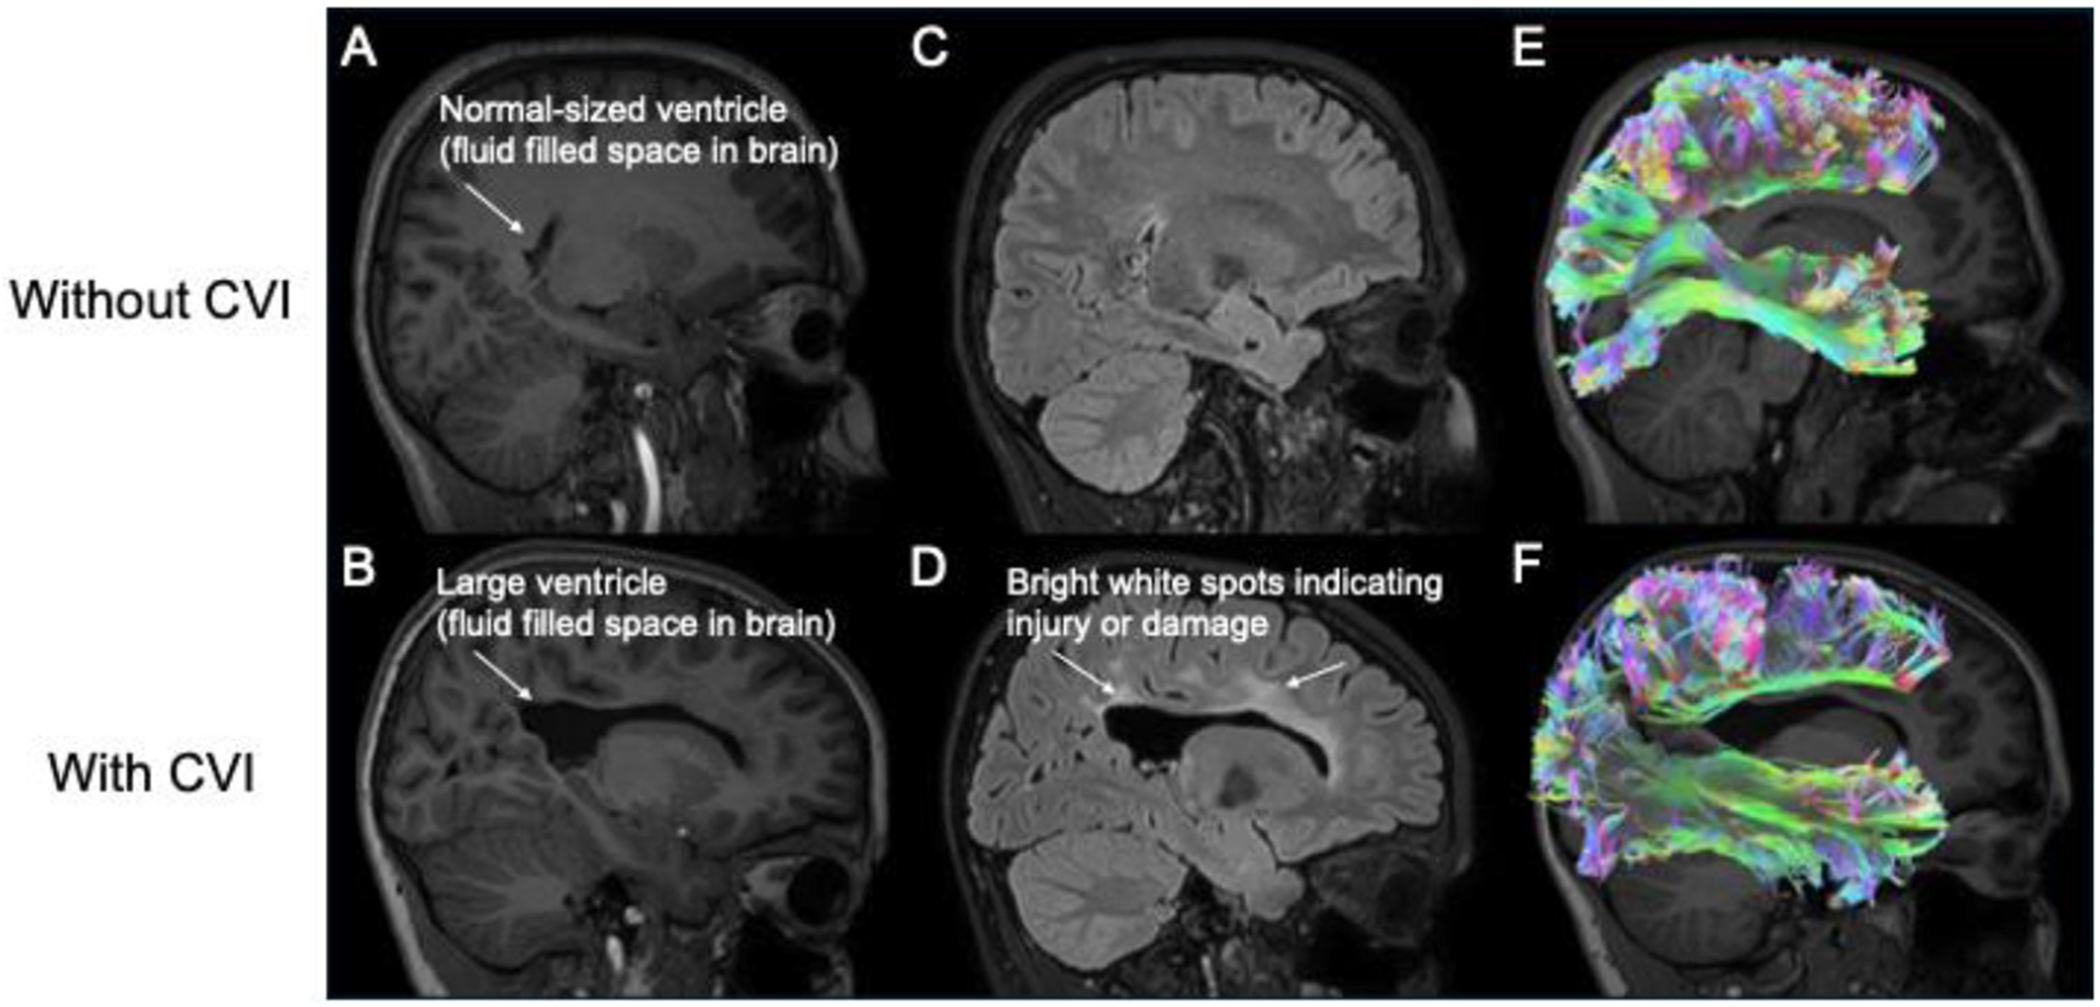

脑性视觉障碍(CVI)是一种由大脑损伤引起的视觉障碍,它使人们难以处理来自眼睛的信息。虽然他们的眼睛可以正常工作,但患有CVI的孩子经常很难找到和识别物体,特别是在混乱或繁忙的地方。临床医生,如眼科专家(研究眼睛和视觉功能)和神经心理学家(研究大脑功能),致力于识别患有CVI的儿童,并在他们患病时给予支持。一个有用的测试是视觉搜索任务,它显示了孩子们是如何寻找东西的。为什么寻找CVI患儿很困难?科学研究人员使用眼球追踪和大脑成像等工具,眼球追踪可以显示儿童在搜索过程中看向哪里,大脑成像可以帮助他们了解大脑各部分是如何协同工作的。通过临床实践和科学研究相结合,我们可以更好地了解CVI儿童如何体验世界,并找到新的方法来帮助他们在日常生活中。

Cerebral visual impairment (CVI) is a visual disorder caused by brain damage that makes it difficult to process information from the eyes. Although their eyes may work fine, children with CVI often struggle to find and recognize objects, especially in messy or busy places. Clinicians, like eye specialists (who study eye and visual functions) and neuropsychologists (who study brain functions) work to identify children with CVI and to support them if they do. One helpful test is a visual search task, which shows how children look for things. Why is searching difficult for children with CVI? Scientific researchers use tools like eye tracking, which shows where children look during a search, and brain imaging, which helps them understand how parts of the brain work together. By combining clinical practice and scientific research, we can better understand how children with CVI experience the world and find new ways to help them in daily life.